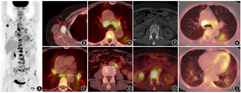

患者女,69岁,因无明显诱因出现胸痛1个月就诊。胸、腹、盆部CT平扫检查发现双肺多发磨玻璃及斑片影,右侧腋窝、纵隔、腹膜后多发肿大淋巴结,多发颈胸腰椎椎体及双侧多根肋骨密度不均;血肿瘤标志物未见异常。患者既往有子宫肌瘤及甲状腺功能减低病史,目前甲状腺激素替代治疗中。因发现肺、淋巴结、骨多发病变,临床怀疑恶性肿瘤可能,遂行18F-FDG PET/CT显像以明确病变性质及分期。18F-FDG PET/CT显像(图1)见双肺多发代谢轻度增高的磨玻璃及斑片影,边界不清,SUVmax 4.0;全身多发代谢增高淋巴结,累及左颈根部、双侧锁骨上、右腋下及胸肌深面、纵隔及双肺门、腹膜后、双侧髂血管旁,淋巴结最大者短径1.6 cm,SUVmax 15.9;扫描野内骨骼大量代谢增高灶,CT上密度不均,SUVmax 12.6,累及脊柱、骨盆、肋骨、胸骨、双侧肱骨、双侧肩胛骨、双侧锁骨、双侧股骨。

本例病变累及全身淋巴结、骨、肺,恶性病变考虑血液系统肿瘤及实体瘤转移,良性病变则主要鉴别结核等全身播散性感染性疾病。因骨骼病变分布随机,未见多个椎体连续性病变或累及椎间盘,亦未见椎旁脓肿形成,骨骼病变未见骨破坏区周围的反应性硬化带或死骨形成,影像上暂无支持结核等感染性疾病的依据,因此首先考虑恶性病变,主要鉴别血液系统肿瘤和实体瘤转移。仔细观察淋巴结形态,可见纵隔及部分腹膜后淋巴结中央有低密度区,部分淋巴结之间有融合;纵隔和肺门淋巴结以气管周围淋巴结受累为主,而淋巴瘤更容易累及的前纵隔区域受累不明显;淋巴结虽累及全身多个淋巴结区,但没有超过2 cm以上或形成大肿物;再看骨的病变,血液系统肿瘤主要为骨髓弥漫性或局灶性浸润,相较实体瘤而言较少对骨质造成破坏,而本例骨骼病变多处可见骨质密度异常。从上述特点来看比较支持实体瘤转移,而血液系统肿瘤的特征较少。若考虑实体瘤淋巴结转移、骨转移,而PET/CT未见明确的原发灶提示(双肺多发边界不清的磨玻璃及斑片影,更像炎性病变而非肿瘤),则要从隐匿性原发肿瘤转移的方向去考虑。

本病例整体来看,膈上淋巴结较腹盆部淋巴结更多、更广泛,膈上淋巴结又以右腋窝及胸肌深面淋巴结更为突出且更有特征,这是乳腺癌最常见的淋巴引流途径,而其他区域受累淋巴结和骨转移也都可用乳腺癌来解释。部分乳腺癌在PET/CT上可以表现为代谢不高,并且当病灶较小时,CT上的密度及形态也不会有异常表现,所以综合考虑可能为右乳腺来源的恶性肿瘤。患者接受了腋窝淋巴结穿刺活组织检查(简称活检),病理检查发现瘤细胞,免疫组织化学(简称免疫组化)检查示转录因子GATA3(+)、雌激素受体(estrogen receptor, ER;+)、孕激素受体(progesterone receptor, PR;+)、人表皮生长因子受体2(human epidermal growth factor receptor 2, HER2;-)、新天门冬氨酸蛋白酶(Napsin A;-)、配对盒基因8(paired box gene 8, Pax8;-)、甲状腺转录因子1(thyroid transcription factor 1, TTF-1;-),结合免疫组化结果考虑为乳腺来源。患者也进行了乳腺钼靶、乳腺超声及乳腺MRI检查,除了双乳增生,均未提示其他异常。临床综合考虑隐匿性乳腺癌广泛转移,患者后续进行了内分泌治疗。